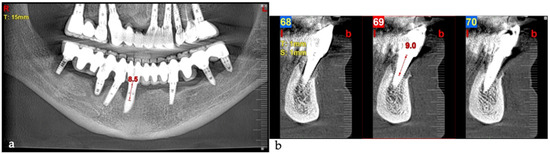

The intraoral examination revealed poor oral hygiene, characterized by significant plaque accumulation (over 65% plaque index) along the gingival margins and interdental areas. The periodontal status evidenced a progressive periodontal disease, with bleeding on probing (BoP) over 60%, mainly around all dental implants; peri-implant tissues possessed a high level of inflammatory condition, with localized swelling, high level of BoP, redness, and suppuration at the site of teeth #46 and #47, indicating local acute inflammation. The probing depth (PD) at site implant #46 exceeded 9 mm at both the mesial and distal sites, and at #47, the mesial site had a PD of 7.8mm, while the distal site showed lower bone loss (Figure 7).

Radiographically (Figure 8), the findings demonstrated full mouth edentulism, rehabilitated with upper and lower bridges and crowns supported by dental implants, as well as bone loss at #37, #46, and #47. The peri-apical radiograph (Figure 7) showed two dental implants, each measuring 13 mm, with bone loss around implant #46 (exceeding 60% of the implant length) and around implant #47 (exceeding 70% of the implant length).

Figure 16. Panoramic radiographic view (a) and cone-beam computed tomography (CBCT) (b), revealing bone loss at baseline at tooth #41, respectively, 8.5 mm and 9.0 mm (red arrows).